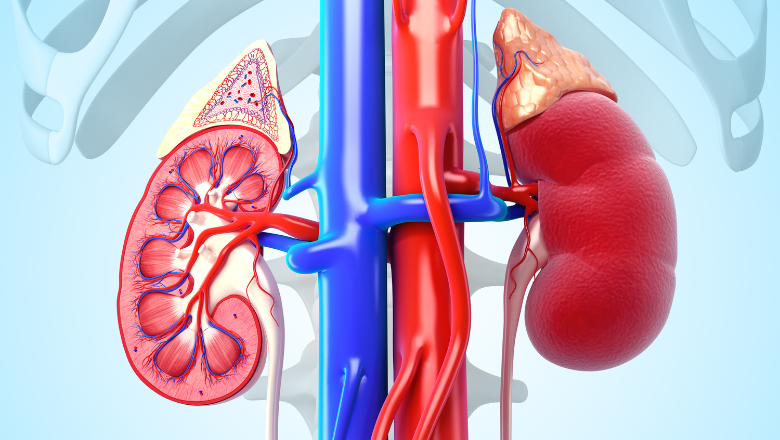

Симптомы подострого гломерулонефрита: фото и описание